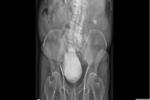

臺大動物醫院分享,一隻烏龜取出5顆結石。(翻攝臺大特殊寵物及野生動物醫學研究室臉書)

結石不算罕見,但一次取出5顆,其中一顆還特別大,可就很少看到了。臺大特殊寵物及野生動物醫學研究室PO文,分享本年度「結石冠軍」,場面驚人。

臺大特殊寵物及野生動物醫學研究室臉書分享,一隻烏龜因嚴重尿結石,被送往臺大動物醫院治療,因數量又多又大,只能進行俗稱「開殼」的腹甲切開術(Plastronotomy)。